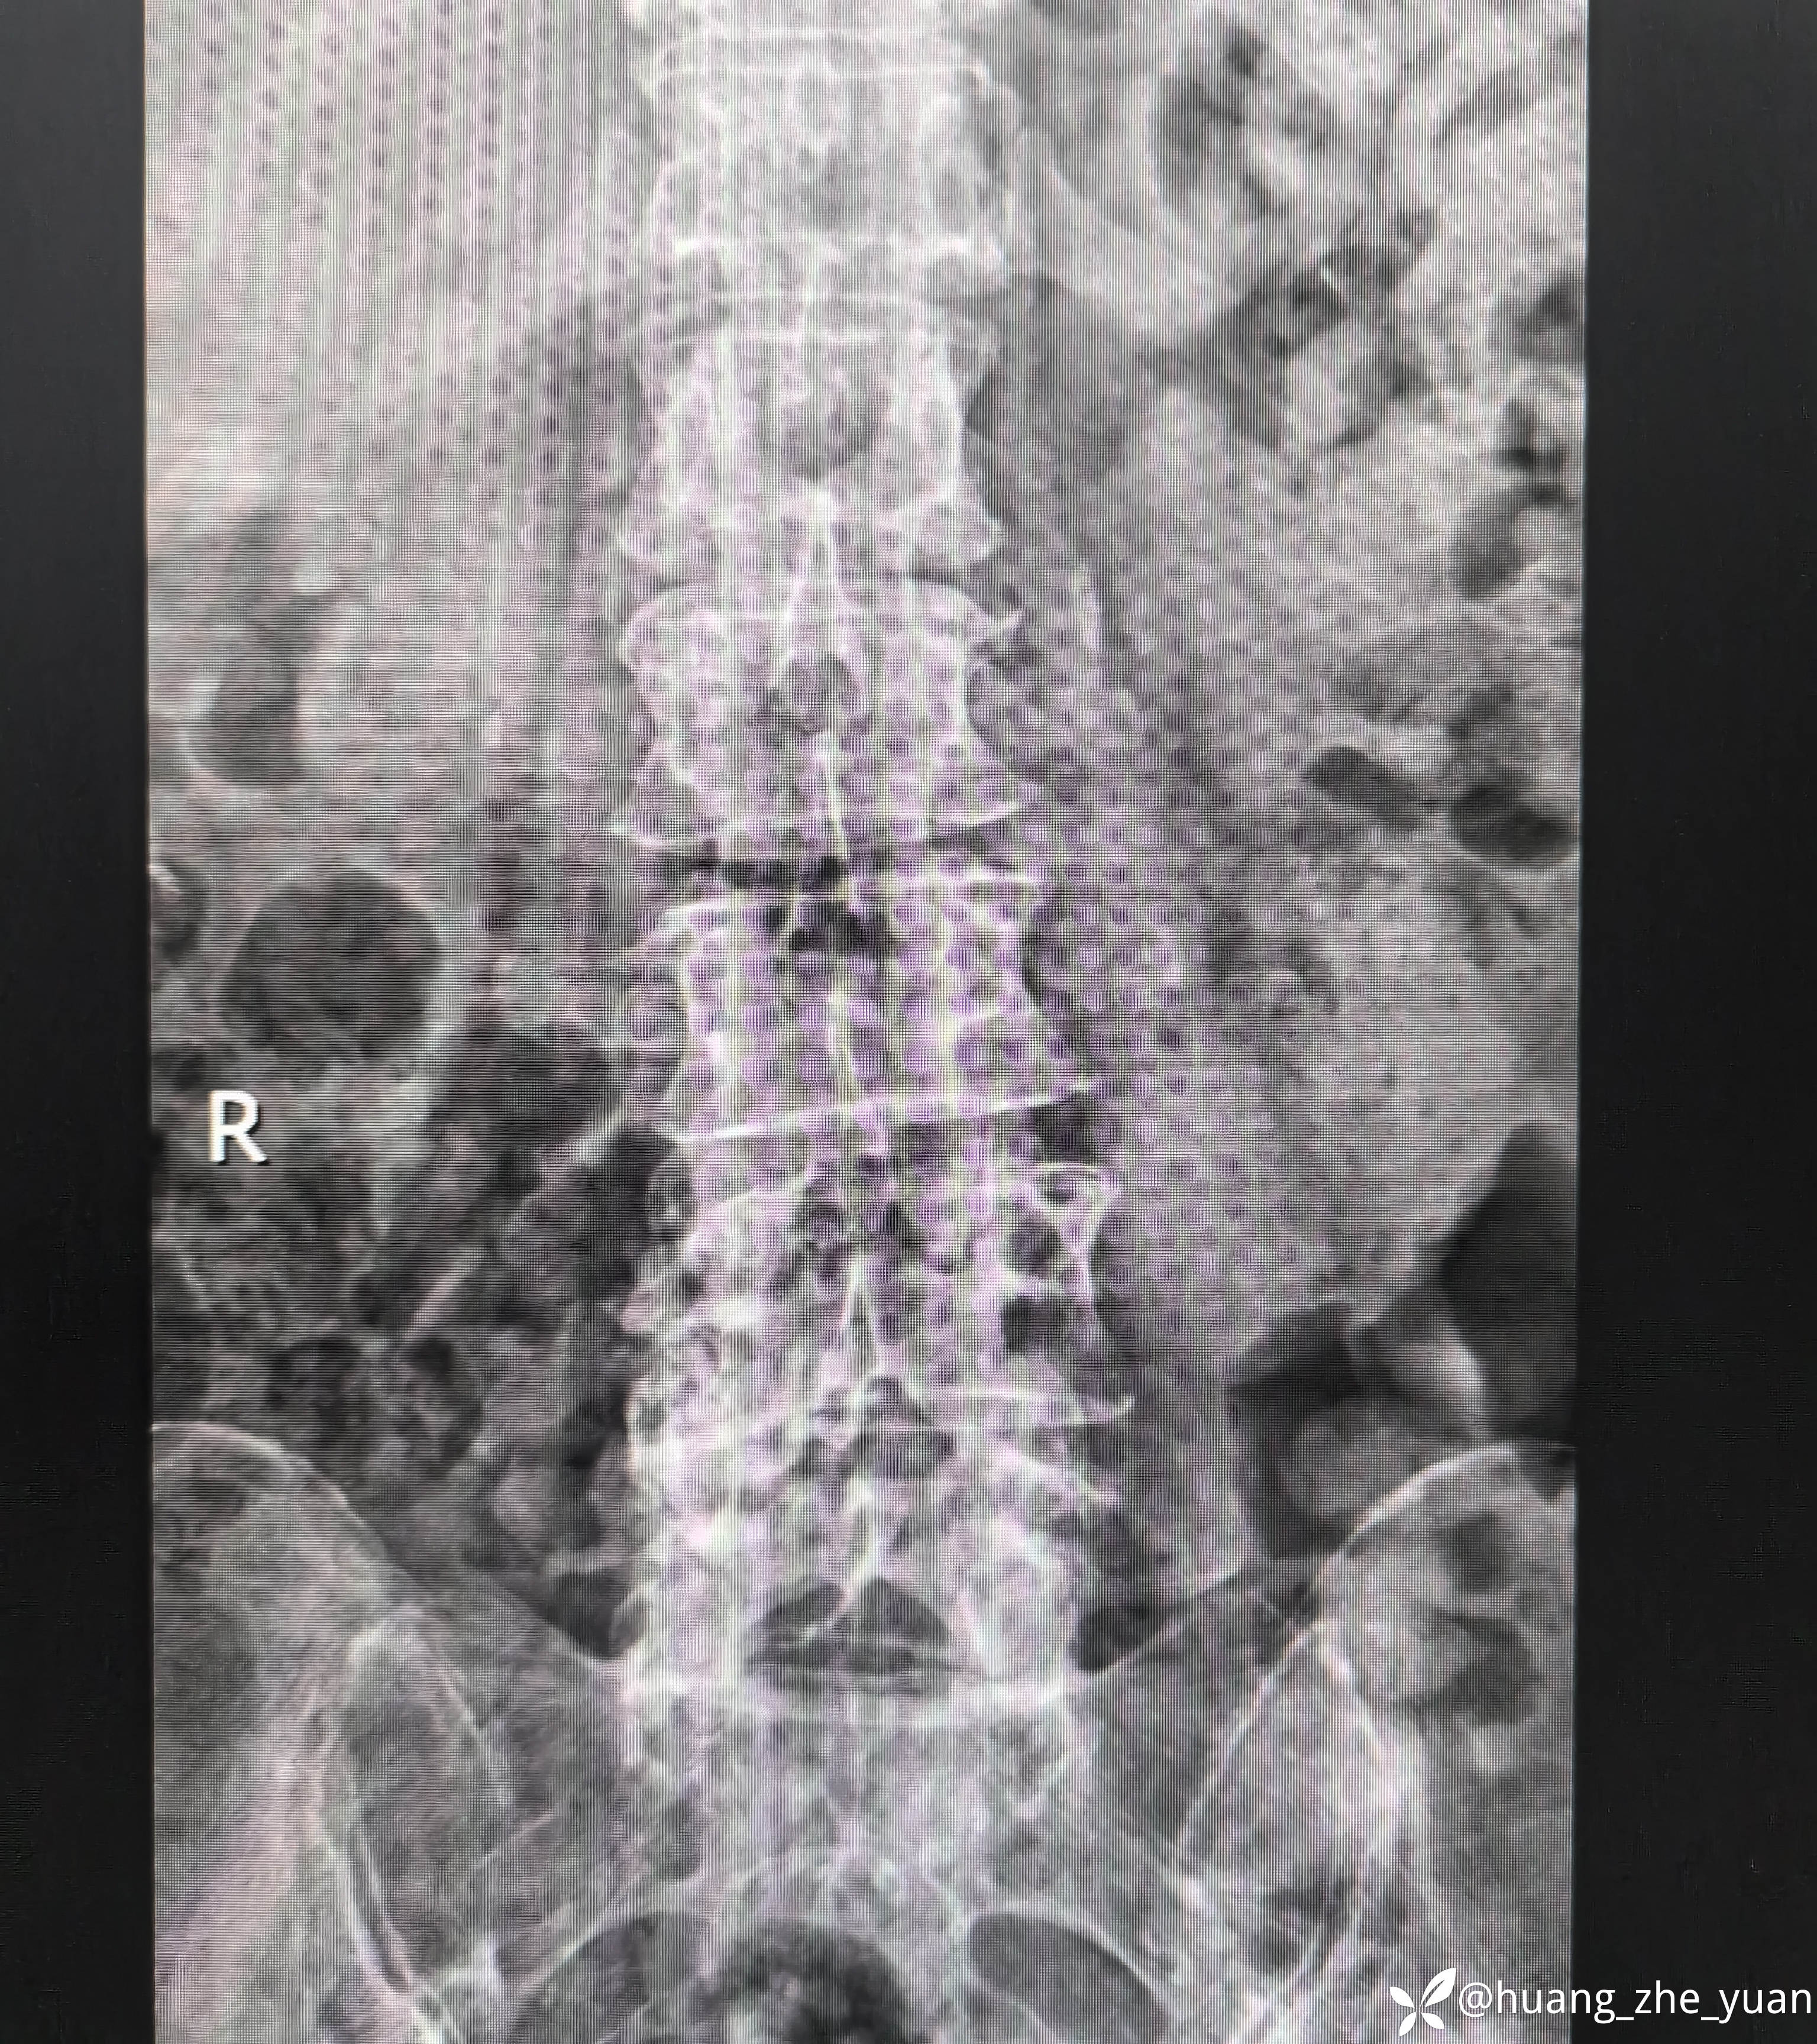

70岁女性,反复右下肢放射痛八个月。合并症:糖尿病,胰岛素泵控制。